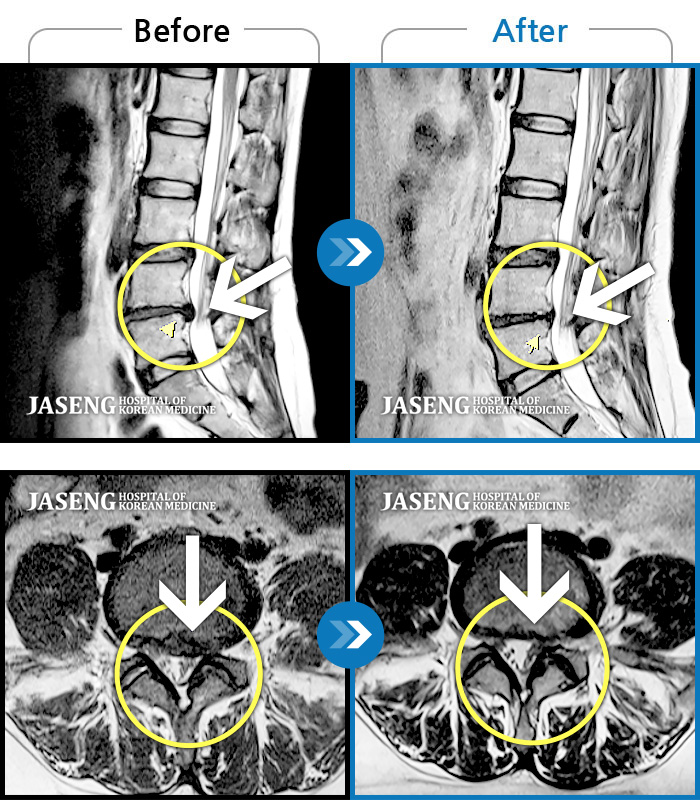

Before

After

환자에게 사전 동의를 받아 동일 조건에서 촬영되었습니다.

개인에 따라 치료 후 부작용이 발생할 수 있으니 의료진과 상담 후 치료를 진행하시기 바랍니다.

허리통증과 좌측 엉치 및 꼬리뼈 까지의 심한 통증으로 일상생활의 어려움 호소

허리통증 및 우측 하지 방사통